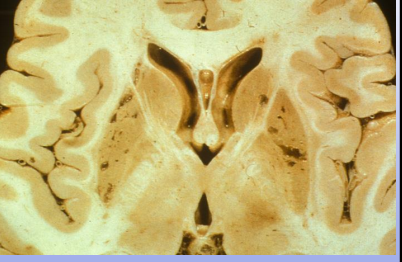

Global cerebral ischemia: end-arterial (watershed) distribution; darker areas (in red circle) are injured due to acute ischemia

MCA distribution

PCA (bilateral)

This is a cross-section of the brain with occipital view

PCA (basilar artery)

MCA infarcts affecting parietal lobe

Both ACA (medially) and MCA (laterally)

Lacunar infarct (small artery); multiple small holes